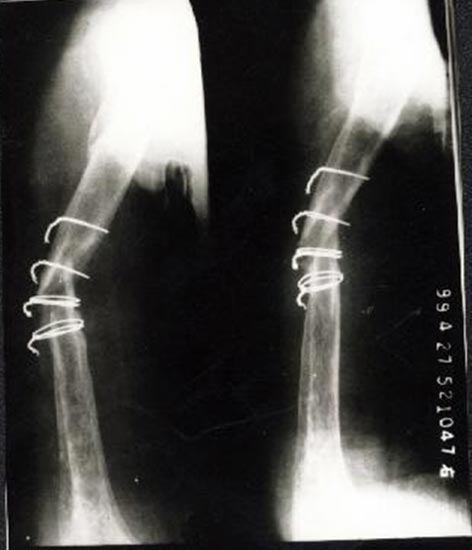

病例二、患者女性,20岁,肱骨中段骨折1年,骨不连形成。

带锁髓内钉固定骨折端提供支撑力,患者自体骨髓细胞经与松质骨和骨生长因子复合,

使没有细胞的植骨材料变成了有细胞的活骨。骨折在8个月后愈合。

手术后去除内固定